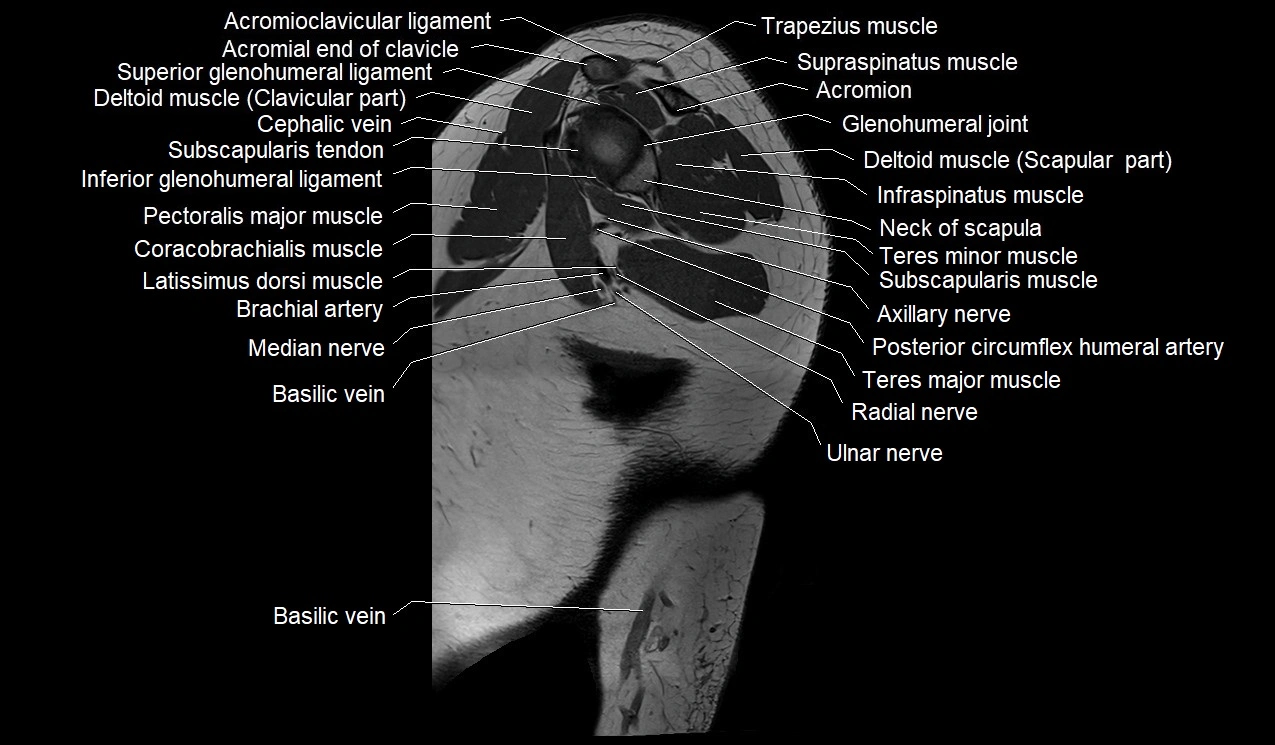

- Acromioclavicular ligament

- Acromion process of scapula

- Axillary nerve

- Basilic vein

- Biceps brachii muscle

- Brachial artery

- Cephalic vein

- Coracobrachialis muscle

- Inferior glenohumeral ligament

- Infraspinatus muscle

- Median nerve

- Neck of scapula

- Pectoralis major muscle

- Posterior circumflex humeral artery

- Radial nerve

- Subscapularis muscle

- Subscapularis tendon

- Superior glenohumeral ligament

- Supraspinatus muscle

- Teres major muscle

- Teres minor muscle

- Ulnar nerve